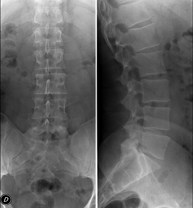

- Lumbar spine X-ray

This technique uses X-ray rendered imaging to examine the lumbar spine. Indicated for: sciatica, trauma, lower back pain.

Tècnica que usa els raigs X a través de la qual s'obtenen imatges de l'abdomen (estómac, intestí prim, intestí gros, fetge, ronyons, bufeta, pelvis òssia, etc.) per al seu estudi. - RX Columna lumbar

Tècnica que usa els raigs X a través de la qual s'obtenen imatges de la columna lumbar per al seu estudi. - TEGD (trànsit esòfag-gastro-duodenal)